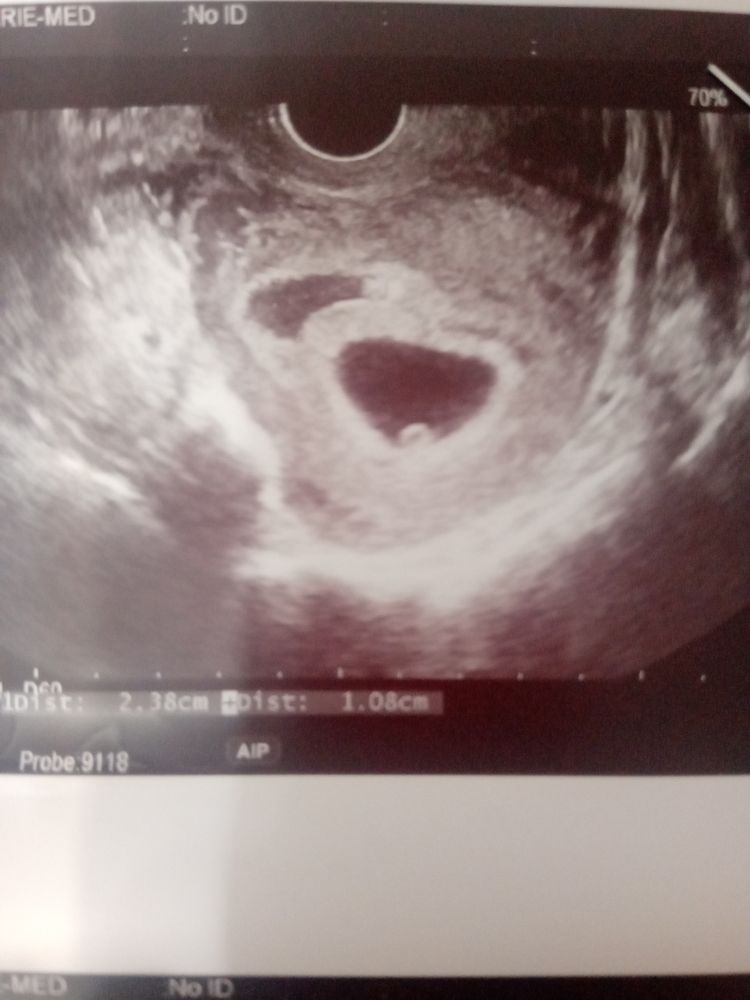

У меня в 7 нед была гематома 24х11х15. Назначили папаверин на ночь и праджисан 200 2 р.д. в 9 нед на УЗИ гематома уменьшилась 15х3 примерно, точно не помню. Короче, лечение работает. Дозу мне уменьшили до 1 раза в день, пока ещё ставлю. Была на скрининге неделю назад, малюсенькая ещё есть, буквально несколько мм, врач сказала даже не обращать внимания.

Вот как выглядела наша гематома на первом УЗИ